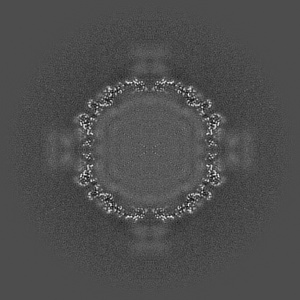

Cryo-EM structure of coxsackievirus A16 A-particle in complex with Fab h1A6.2

Single-particle3.38 Å